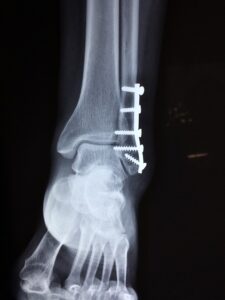

Złamanie nogi, zwłaszcza kości piszczelowej czy podudzia, to bolesne doświadczenie, wymagające kompleksowego podejścia. Jeśli dojdzie do tego w wypadku, warto wiedzieć, że istnieje możliwość ubiegania się o odszkodowanie. Procedura może być skomplikowana, jednak warto podjąć wysiłek, by uzyskać sprawiedliwe świadczenia.

Najpierw należy zgłosić wypadek sprawcy, aby otrzymać odszkodowanie z jego ubezpieczenia OC. Złamanie kości piszczelowej to poważna sytuacja, wymagająca leczenia, rehabilitacji i poniesienia wielu wydatków. Dochodzenie odszkodowania obejmuje także zadośćuczynienie za cierpienie i straty.

W trakcie procesu warto unikać sytuacji, gdzie sprawca może odmówić wypłaty odszkodowania. Niebagatelne jest także uzyskanie najwyższego możliwego świadczenia, zwłaszcza przy wieloodłamowym złamaniu kości. Obejmuje to jednorazowe odszkodowanie oraz rentę dostosowaną do poziomu pensji.